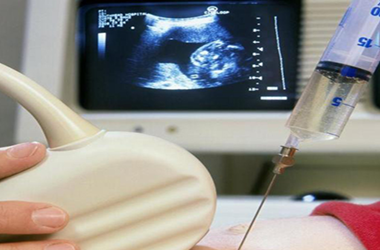

医生在监测排卵的时候,一方面通过超声观察卵泡的大小,另一方面看雌激素的水平与卵泡的发育是否一致。当卵泡接近成熟时,一个卵泡大约200pg/ml,如果基本复合,那么说明卵泡成熟了。